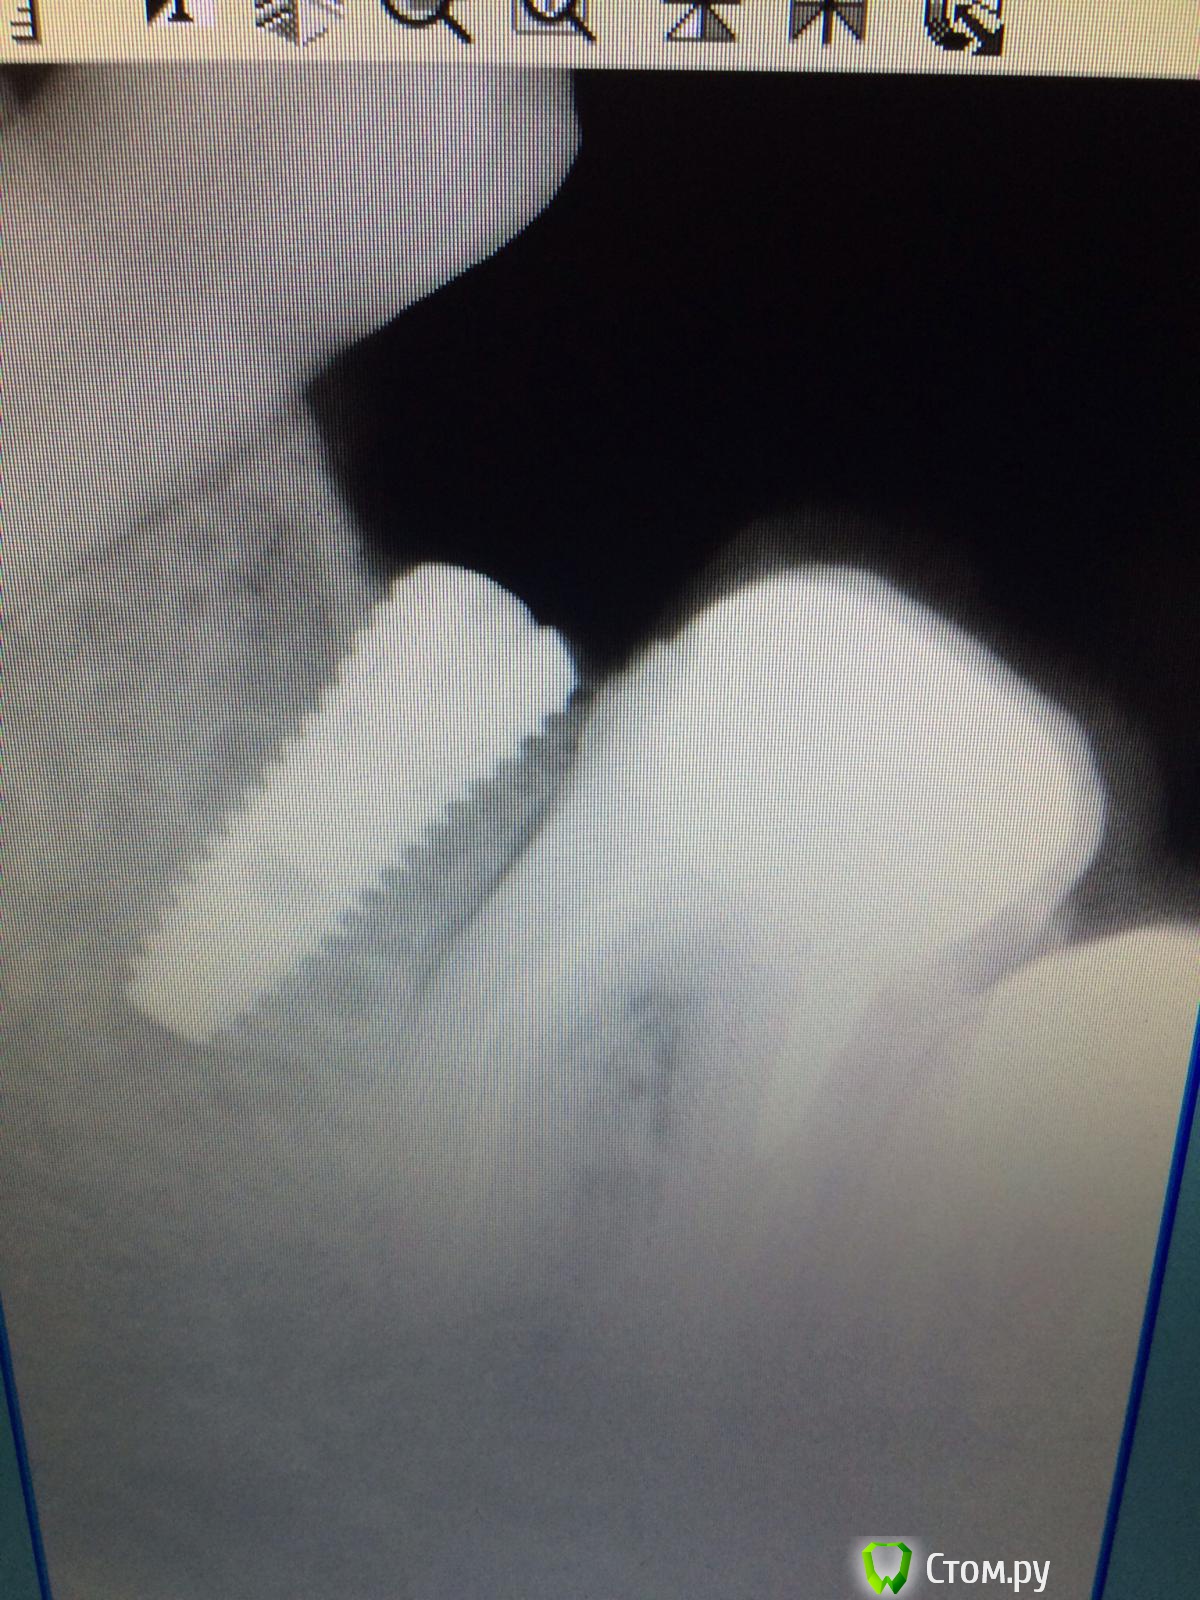

Vadim09 Опубликовано 4 октября, 2014 Автор Поделиться Опубликовано 4 октября, 2014 (изменено) Расщепление не надо- может лопнуть. Ложе будете готовить пилотом пройдите, потом остеотомами работайте до нужного размера ,сверху стружки сыпануть.Спасибо, воспользовался вашим советом, кортикалка лопнула у шейки немног, пдсыпал биоосса и покрыл мембраной Изменено 4 октября, 2014 пользователем Vadim09 Ссылка на комментарий

k.t.m. Опубликовано 4 октября, 2014 Поделиться Опубликовано 4 октября, 2014 Спасибо, воспользовался вашим советом, кортикалка лопнула у шейки немног, пдсыпал биоосса и покрыл мембранойimage.jpgimage.jpgнадо было заглубить и более медиальнее 3 Ссылка на комментарий

faity Опубликовано 5 октября, 2014 Поделиться Опубликовано 5 октября, 2014 Спасибо, воспользовался вашим советом, кортикалка лопнула у шейки немног, пдсыпал биоосса и покрыл мембранойimage.jpgimage.jpgпожалуйста, обращайтесь. ждем снимков после Ссылка на комментарий